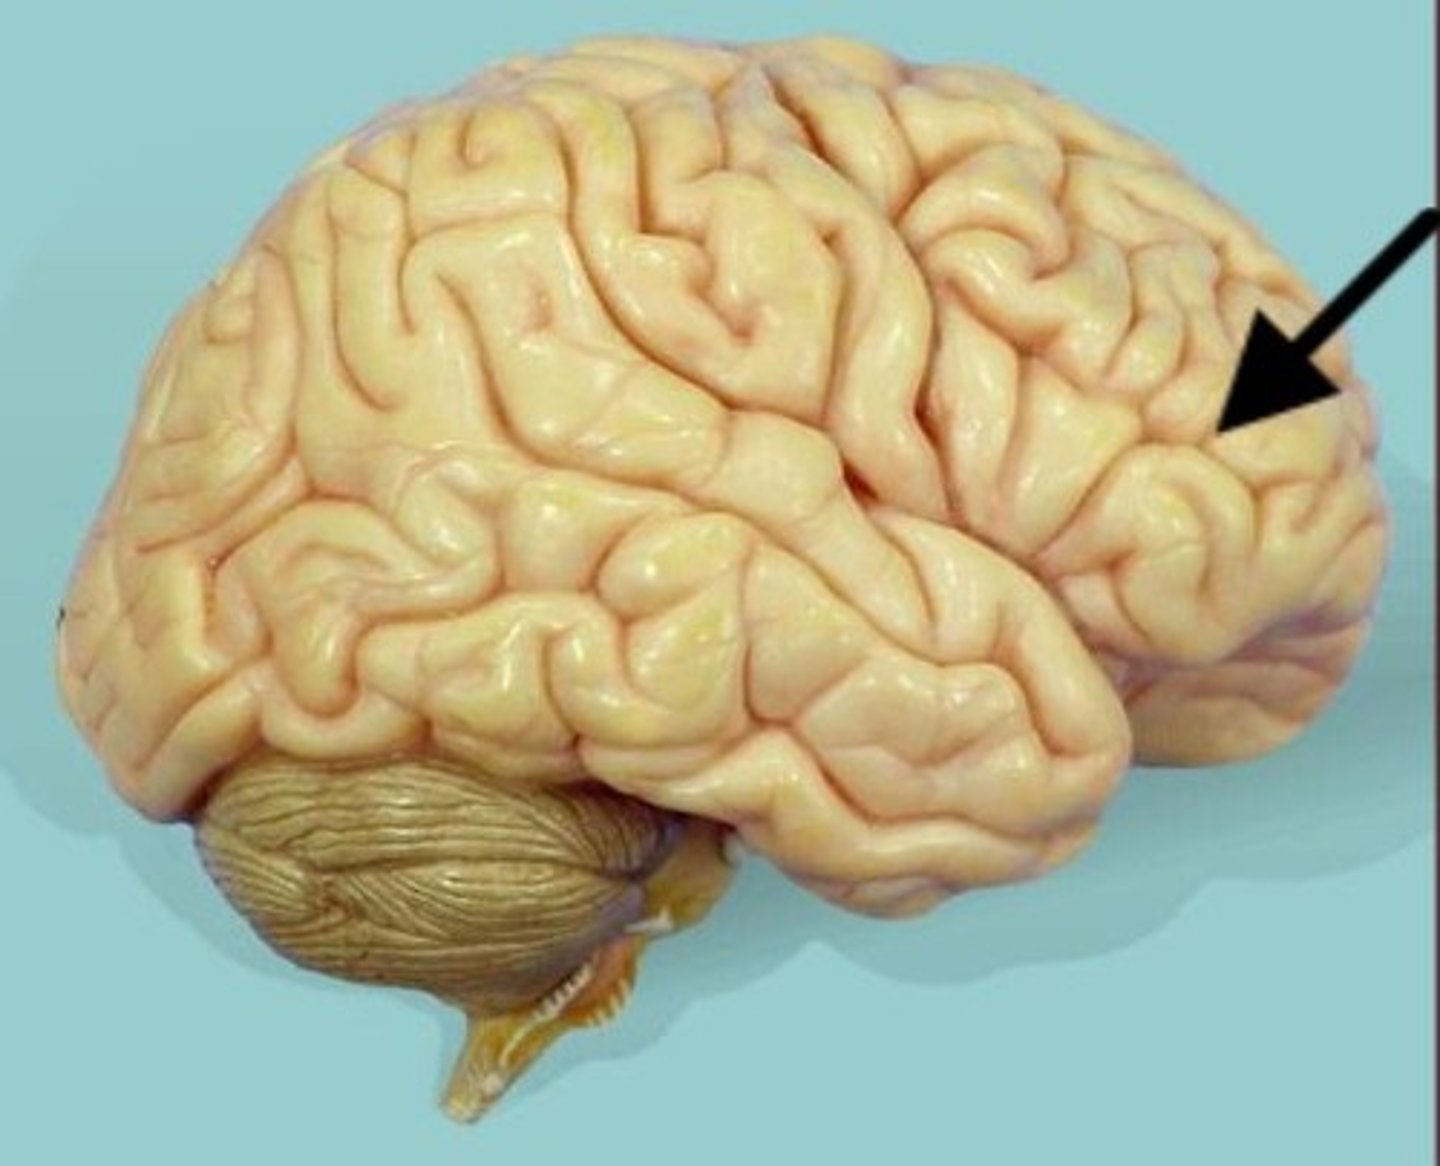

frontal lobe

lateral sulcus

pareital lobe

occipital lobe

transverse fissure

separates cerebrum from cerebellum

temporal lobe

cerebellum